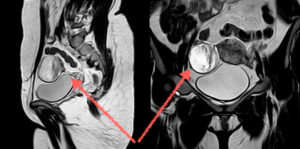

МРТ малого таза. Стрелкой указан яичник и геморрагический компонент в нем

МРТ малого таза.Двурогая матка. Частая причина бесплодия. Стрелками указаны рога матки